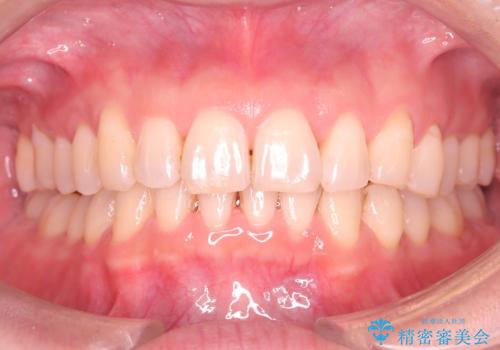

【インビザライン】前歯のねじれを治したい

- 前歯のガタガタを主訴に来院されました。

叢生の量は軽度でしたが臼歯の遠心移動を行い、インビザラインにて治療をしました。

叢生の改善に必要なスペースは遠心移動やIPRで作ることが可能です。今回は遠心移動をメインにスペースを作って叢生の改善を行いました。